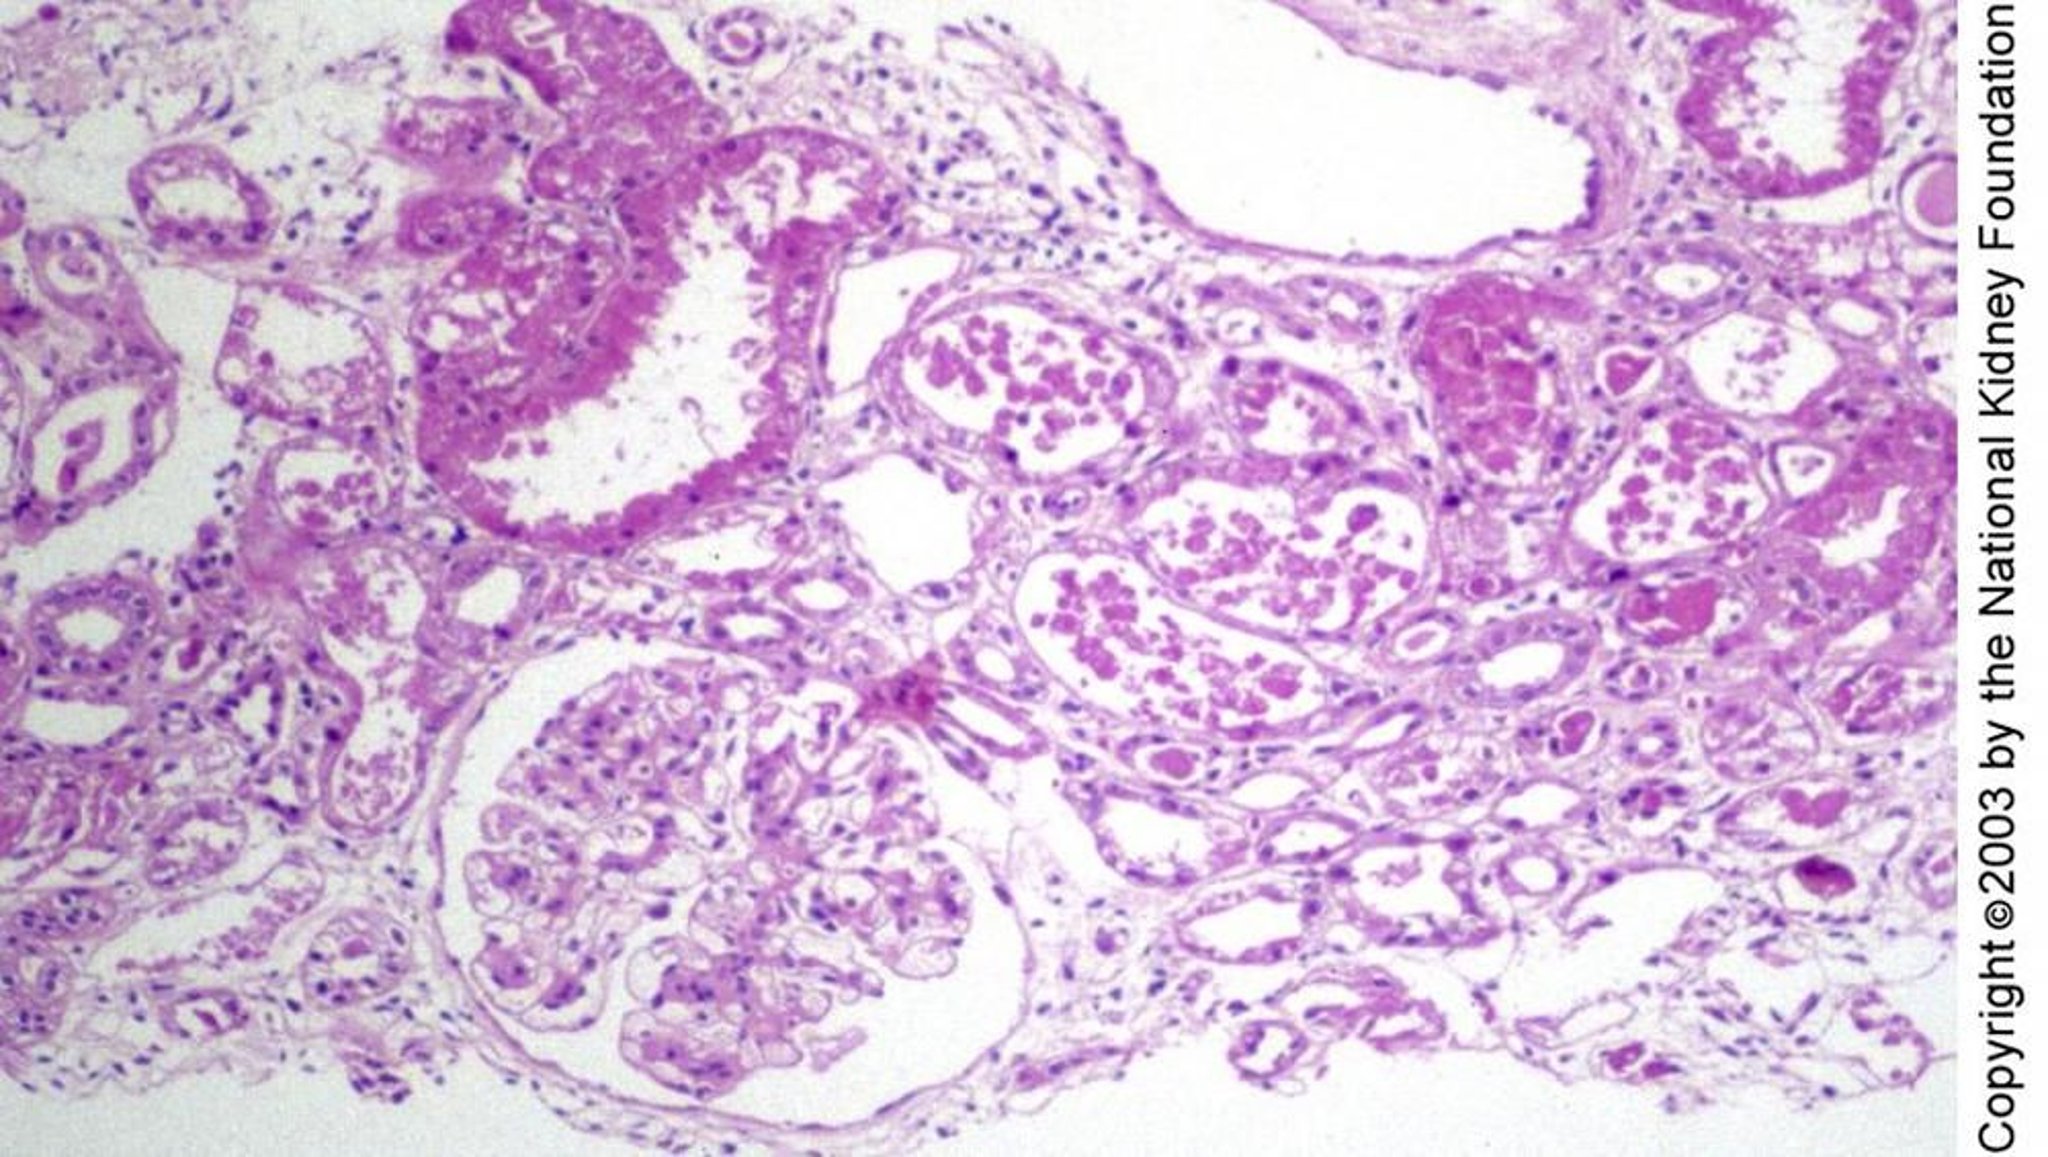

Nécrose tubulaire aiguë

Une lésion tubulaire encas de nécrose tubulaire aiguë peut se manifester histologiquement sous la forme d'un épithélium tubulaire aplati en régénération sans nécrose, comme on peut le voir à droite du glomérule, d'une hémorragie et d'une dégénérescence de cellules isolées, comme on peut le voir en haut à gauche ou d'une nécrose franche, comme on peut le voir au milieu de l'image (coloration à l'acide périodique Schiff, ×100).

Image fournie par Agnes Fogo, MD, and the American Journal of Kidney Diseases' Atlas of Renal Pathology (voir www.ajkd.org).